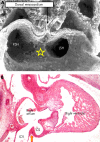

Figure 19

This section from a human embryo at Carnegie stage 14 is comparable to the picture of the mouse heart shown in fig 18. This section, however, has been stained with an antibody to the nodose ganglion of the chick, which recognises the developing atrioventricular conduction tissues, staining them brown. As can be seen, the conduction tissues at this stage form a ring around the primary interventricular foramen (double headed arrow), the inferior part of the ring marking the crest of the developing muscular ventricular septum, and the superior part occupying the right atrioventricular junction. Thus, at this stage the ring is both interventricular and atrioventricular. The section is taken between the unfused atrioventricular cushions, showing that most of the circumference of the atrioventricular canal is supported by the developing left ventricle (black bracket).